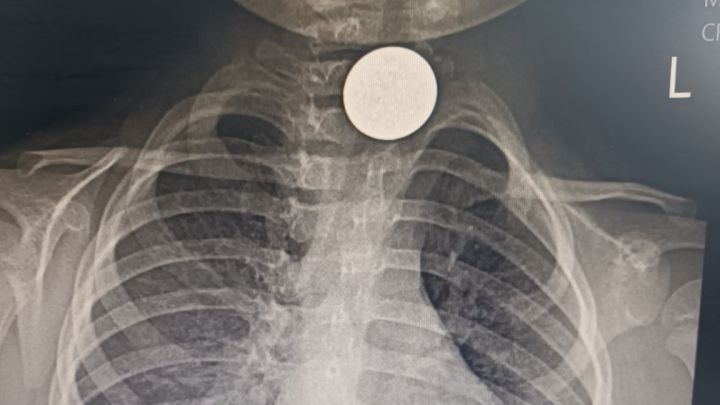

Допреди десетина дни, когато внезапно започва да вдига необяснимо висока температура. „Отиваме при личната – един антибиотик. Спада. После пак вдига – втори антибиотик. И не минава. Усъмни се да няма нещо в белия дроб и пак ни насочи за снимка“, разказва бащата. При снимката на белия дроб монетата лъсва точно на входа на хранопровода – в края на гърлото. Лаборантката се учудва – да не би детето да е било с медальон, който не е свален преди рентгена? Тогава майката се сеща за играта с монети и се изяснява, че това е глътнатата стотинка - заклещена дълбоко навътре в гърлото, в самото начало на хранопровода.![]()

Монетата е извадена в УНГ отделението на УМБАЛ Бургас от доц. д-р Даниел Петков и д-р Ивайло Илиев. „Предполагаме, че когато майката се опитала да извади монетата от гърлото, я е избутала навътре. Учудващо е как толкова дълго време детето се е хранило въпреки нея. Чуждото тяло е предизвикало хронично възпаление на хранопровода, оттам и необяснимата температура. При подобни случаи има голям риск от перфорация и сериозни усложнения, които могат да доведат дори до летален изход“, посочват лекарите.